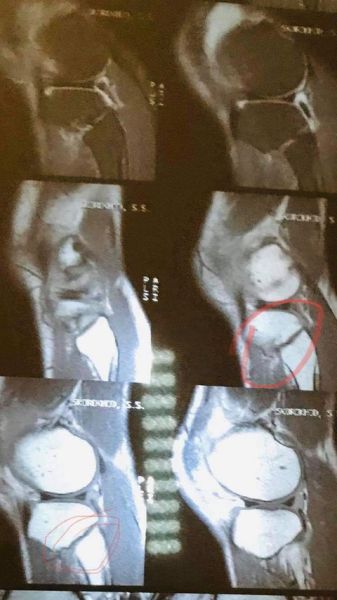

— Я получил травму на тренировке. После выздоровления готов в дальнейшем договариваться о проведении боя. Буду рад подраться с Турсынбаем, мы сделаем зрелищный бой! Сейчас прохожу курс реабилитации на коленный сустав, работаю со специалистами для скорейшего выздоровления, чтобы приступить к тренировкам, — сообщил украинец.

Также он показал фото, подтверждающее травму — посмотреть его можно ниже.